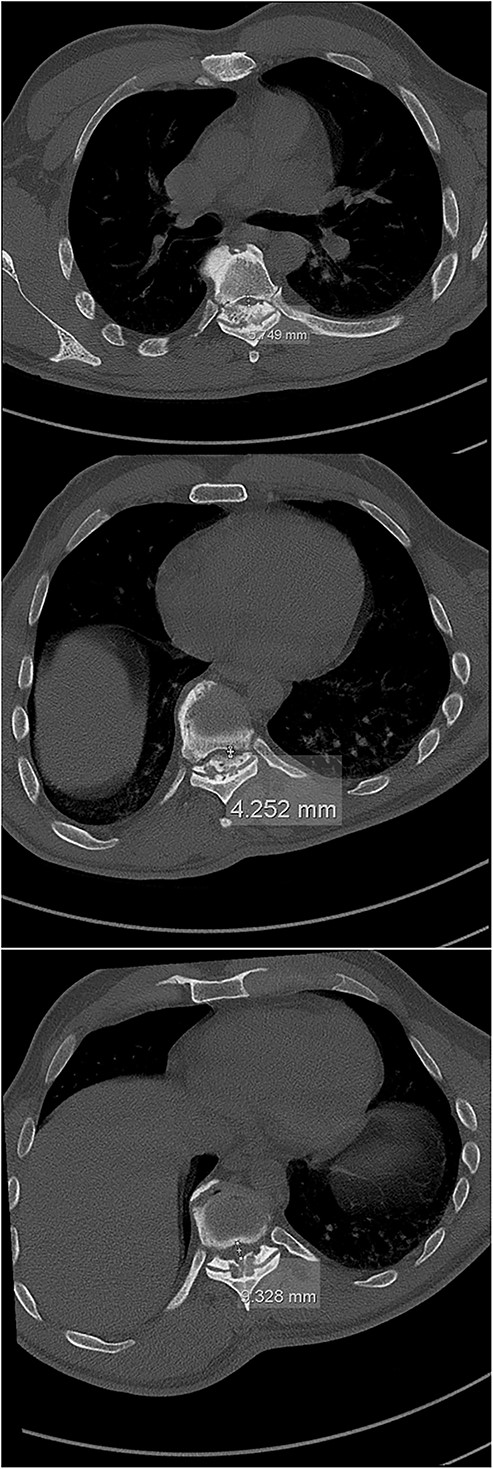

The imaging studies revealed thoracic kyphoscoliosis (with a kyphotic curve of 50°, left upper-thoracic curve of 40° and right lower-thoracic curve of 25°) and significant stenosis of the thoracic part of the spinal canal (particularly at levels Th6, Th9 and Th11) due to severely ankylosed ligamentum flavum (OLF) and the concomitant degeneration of the facets (Figs 1 and 2). Imaging indicated thoracic myelopathy (Fig. 3). We performed emergent posterior wide laminectomy using an ultrasound bone scalpel, and a partial correction of the deformity by instrumented spinal fusion (Th6-Th12). The surgery was performed by the senior author (N.H.).

The initial CT scan (axial views), showing the width of the spinal canal at Th6 (above), Th9 (middle) and Th11 (below).

Computed tomography (CT) is considered the most useful diagnostic imaging modality in identifying the ossification of the spinal ligaments, including the OLF [3, 8]. In severe cases, the ossification can also include the dorsal area of the dura, making the surgical treatment of the OLF very challenging, with a high risk of a dural compromise and leakage of the cerebrospinal fluid [2, 5, 8, 10]. However, this was not the case with our patient.